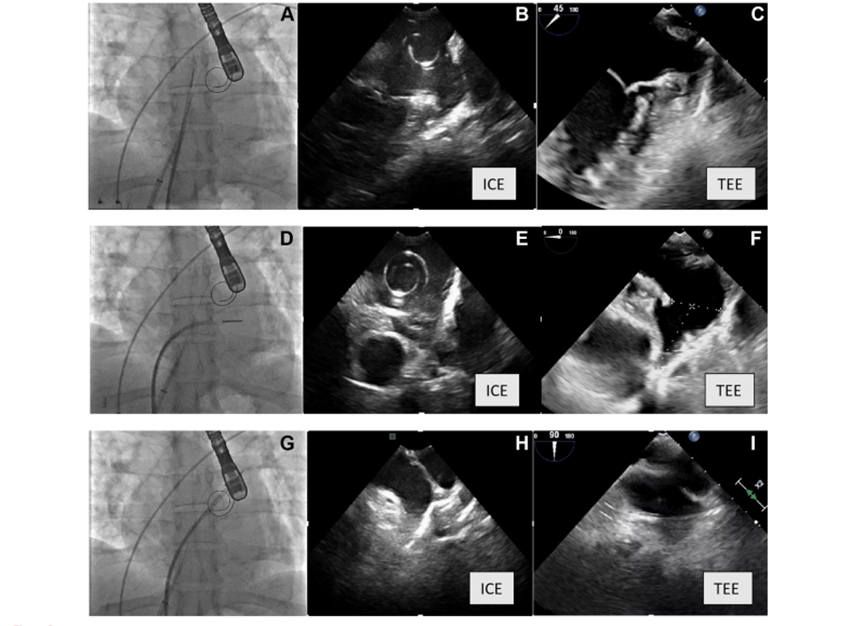

共识也强烈建议在所有LAAC中使用术中影像学指导。术中影像对于排除左房血栓、监测心包积液、指导房间隔穿刺、封堵器植入、稳定性判断、评估压缩比和残余漏的可视化以及医源性房间隔缺损的评估必不可少;不建议仅进行X线透视而不使用TEE或ICE。

图2. 荧光透视图上的相应图像(显示心内超声心动图[ICE]探头位置)、ICE视图和相应的经食管超声心动图同一患者的超声心动图(TEE)视图。(A) 荧光镜检查显示ICE探针位于左心房的后屈曲位置(也显示VersaCross导线位于左心房),(B)左心房后弯位置的ICE探头的图像,(C)经食管超声心动图45°视图的图像。(D) 荧光镜检查显示ICE探头位于左心房中的鞘上位置,(E)来自鞘上左心房位置的ICE探针的图像,(F)来自TEE的0°视图图像。(G) 荧光镜检查显示ICE探头在左上肺静脉中,(H)来自左上肺血管中的ICE探针的图像,(I)来自TEE的90°视图的图像。